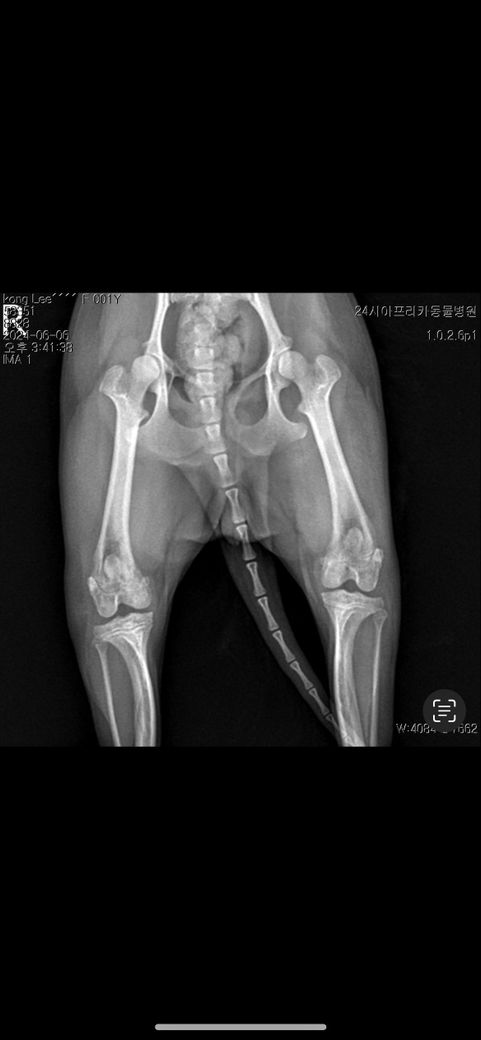

양쪽슬개골이랑 한쪽 십자인대돌아갔다해서 수술 한 상태인데 다른동물병원에서는 이 사진을 보고 십자인대를 한줄 모르더라구요 엑스레이상으로는 확인이 안되나요?십자인대 수술 된건가요?..

(수술전)